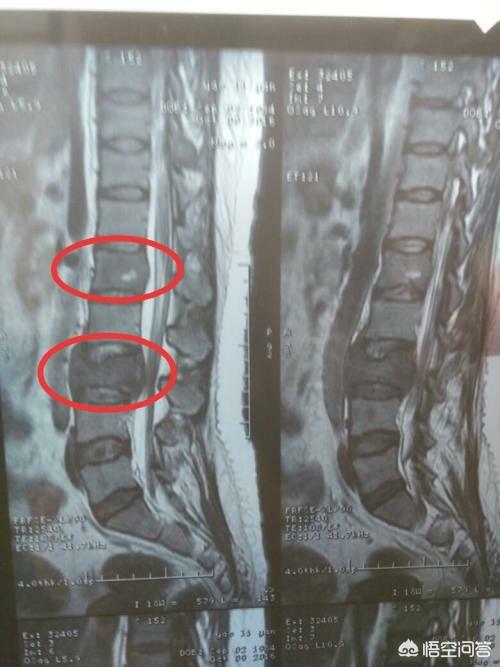

Un homme de 46 ans a été vu en consultation pour une douleur persistante dans le bas du dos. On pensait que cette douleur était due à une hernie discale. Une radiographie a été effectuée et n'a révélé aucune anomalie. Les métastases osseuses provoquant une légère destruction osseuse sont invisibles à la radiographie, de même qu'une hernie discale. Je n'ai donc pas particulièrement pensé à la possibilité d'une métastase. Une semaine plus tard, comme il n'y avait toujours pas d'amélioration, il est venu passer un scanner et a découvert qu'une vertèbre lombaire avait été rongée. En voyant une telle image, le médecin spécialiste de l'imagerie a dû penser à la possibilité de métastases et a suggéré au patient de passer un scanner du thorax, et effectivement, il y avait une masse dans les poumons, qui a été considérée comme une métastase osseuse d'un cancer du poumon, ce qui a été confirmé par la pathologie plus tard.

Bien qu'il existe certaines caractéristiques de la douleur chez les patients atteints de métastases osseuses dues à un cancer, vous pouvez également constater que certains symptômes interfèrent avec la maladie courante.Si le patient se produit, la métastase osseuse de la colonne vertébrale stimule les nerfs, il est alors facile pour le médecin ou le patient de mal diagnostiquer les symptômes induits par la hernie discale, et à ce moment-là, en tant que patient, le corps a des anomalies, nous devrions demander l'aide du médecin en temps opportun, et en tant que médecin d'essayer de communiquer avec le patient, de faire quelques examens relativement de haute qualité, essayer d'écarter le risque de métastase osseuse, comme pour les douleurs dorsales à long terme des personnes âgées, nous recommandons souvent que l'IRM au lieu de l'examen radiographique, et le mal de dos du patient, le mal de dos du patient est très élevé. Par exemple, pour les personnes âgées souffrant de lombalgies chroniques, nous recommandons souvent de leur faire passer une imagerie par résonance magnétique (IRM) plutôt qu'une radiographie.